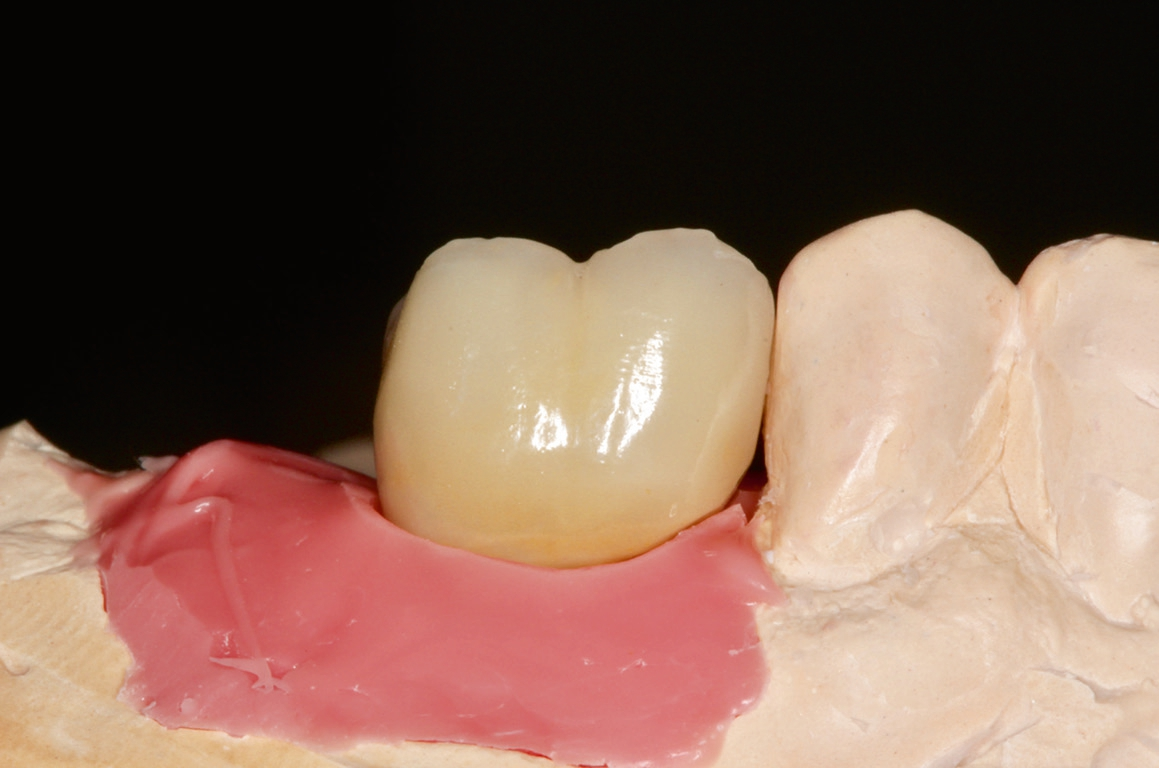

Die Übertragung der Implantatposition ins zahntechnische Laboratorium wird mittels offener Abformung mit individuellem Löffel und einem stabilen Polyäthermaterial vorgenommen. Die achsgerechte Position des Implantates ermöglichte die Anfertigung einer transocclusal verschraubten, verblendeten Zirkonoxidkrone auf einer Klebebasis. Die Besonderheit der Konstruktion ist dabei, dass das Metall der Klebebasis bei der fertigen Konstruktion komplett von Zirkon umschlossen ist. Dies erfordert eine hohe technische Präzision und eine spezielle „Verklebehilfe“ im Labor. Zur ersten Einprobe der Krone beim Patienten befestigen wir die Krone zunächst nur provisorisch auf der Klebebasis. Dies stellt sicher, dass sie bei eventuell notwendigen Korrekturen leicht gelöst und erneut gebrannt werden kann. Ist die Krone in Farbe und Form fertig gestellt, so muss sichergestellt sein, dass die endgültige Verklebung exakt in der gleichen Position auf der Klebebasis erfolgt, wie die zuvor einprobierte. Dafür fertigen wir einen Kunststoffschlüssel.

Vor Eingliederung der Krone wird die Hygienefähigkeit geprüft und sichergestellt, dass zukünftig in Okklusion und Artikulation keine traumatischen Kräfte auf die Restauration wirken. Nach Anziehen des erforderlichen Drehmoments wird der Schraubenkanal mit Teflonband gefüllt und ein okklusaler Verschluss mit Komposit vorgenommen.